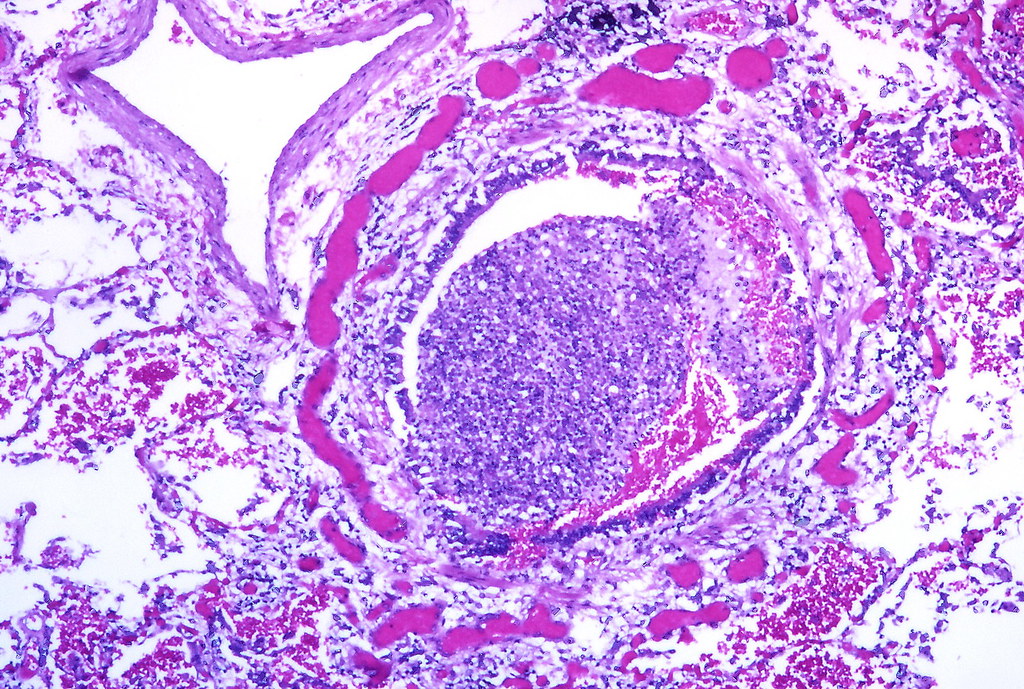

From www.flickr.com

Bronchopneumonia, early Acute bronchiolitis with mild acut… Flickr Is Steam Good For Bronchiolitis Natural and home remedies — such as steam inhalation, honey and lemon, and garlic — may help manage the symptoms of bronchitis. Steam helps loosen the mucus so you can get rid of it. Drink plenty of fluids to thin mucus, use a humidifier or inhale steam to ease breathing, and avoid lung irritants such as smoke and. Moisturizing and. Is Steam Good For Bronchiolitis.